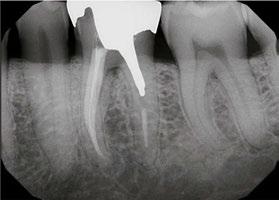

Case 2: Pre-op and diagnosis: A 52-year-old female presented with a chief complaint of pain to hot and cold. Pulpal sensitivity testing on tooth No. 31 revealed a lingering, aching response to thermal testing. A clinical exam revealed a small crack extending from the occlusal resin over the distal marginal ridge. Probing depths around No. 31 were all <3 mm. No. 31 was diagnosed symptomatic irreversible pulpitis with symptomatic apical periodontitis. A pre-op small FOV CBCT revealed No. 31 to have a C-shaped canal morphology. Two treatment options were discussed with the patient: 1) Tooth No. 31 non-surgical root canal therapy or 2) No. 31 extraction. The patient elected No. 31 non-surgical root canal therapy (NSRCT). Treatment: No. 31 NSRCT, the patient was anesthetized with 68 mg Lidocaine with 0.034 mg EPI via IAN and 68 mg Septocaine with 0.017 mg EPI via buccal Infiltration. Rubber dam isolation was utilized, and access was prepared. Due to the C-shaped canal morphology, only two canals could be identified. Prior to placement of the SoundSeal platform, a small amount of bonding agent was placed over the crack along the distal marginal ridge and distal portion of the pulp chamber. The SoundSeal platform was securely placed to create a vacuum seal. The two canals were negotiated to achieve patency by alternating rotary instrumentation and the GentleWave CleanFlow Procedure Instrument for 30-40 seconds to thoroughly debride the internal anatomy. The mesial canal was instrumented to a Master Apical File of 20/.04, while the distal canal to a 25/.04 Master Apical File. Due to the larger and more irregular canal morphology of the distal canal, various-sized gutta-percha cones were used to gauge the size to be used for obturation. The mesial canal was obturated with a Sealer-based obturation method with High Flow BC Sealer and a single 20/.04 master cone. The distal canal was obturated with High Flow BC Sealer and Warm Vertical Compaction. With the aid of the GentleWave and the CleanFlow Procedure Instrument, the C-Shaped canal anatomy was more deeply cleaned, pulp tissue more thoroughly removed, and this case was completed in a single visit which would have been much more difficult to accomplish with traditional endodontic therapy.

10 Endodontic Practice US Volume 17 Number 1 COVER STORY